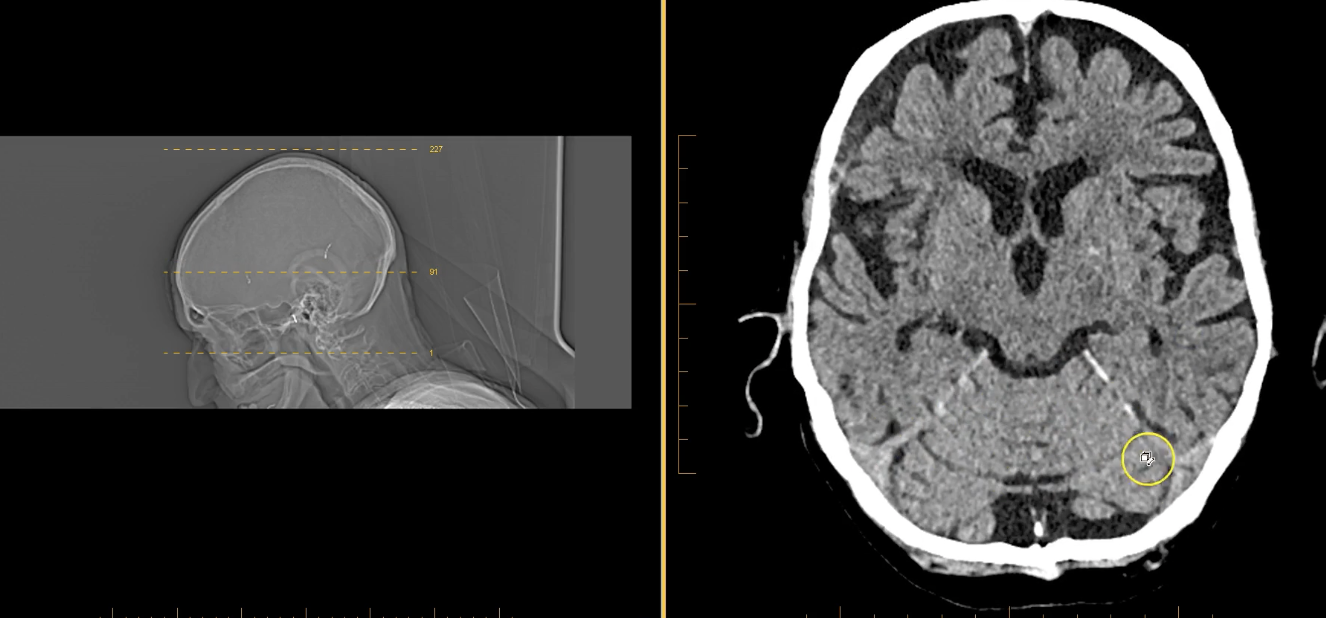

term image

calcified choroid plxus in lateral ventricles